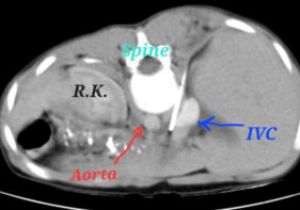

दर्द ने छुड़ाया स्कूल, रेडियोलॉजी विभाग ने लौटाई स्कूल जाने की आस

23 Apr, 2023 11:16 AM IST | SAMWADINDIA.INरायपुर डॉ. भीमराव अम्बेडकर स्मृति चिकित्सालय के रेडियोलॉजी विभाग में बिना चीर-फाड़ के क्रॉनिक पैंक्रियाटाइटिस की...